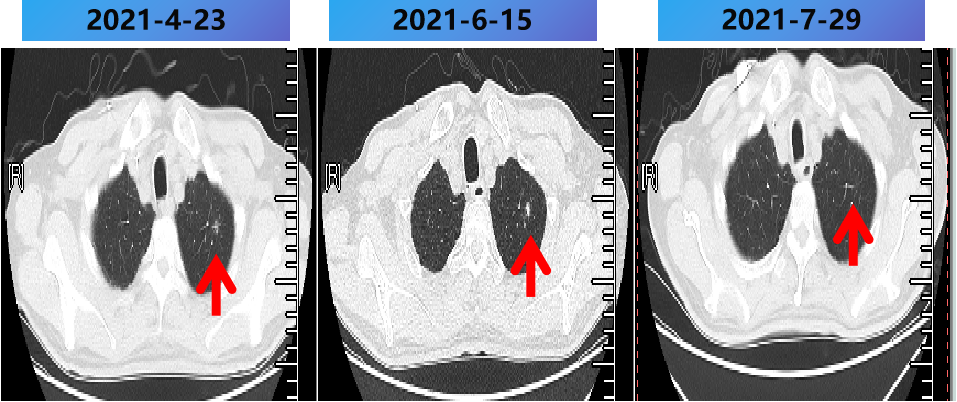

2021-2-25至2021-7-25 更换方案为bev+伊立替康+雷替曲塞 9周期,肺内病灶稳定(SD)。

西妥昔单抗联合阿帕替尼+PD-1抑制剂 2周期,出现蛋白尿,后调整为西妥昔单抗联合PD-1抑制剂,评价PD。